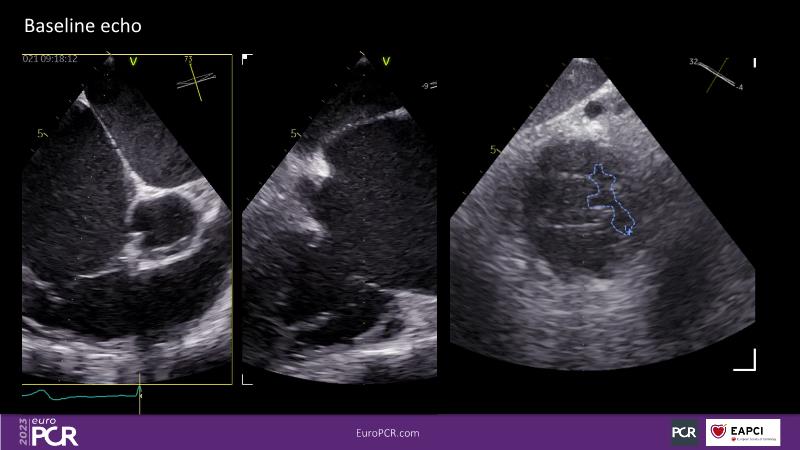

Watch this session to discuss exciting cases of tricuspid regurgitation, learn about the proposed new integrated classification for tricuspid regurgitation and enjoy a live presentation of the PASCAL Precision Repair System using a beating heart simulator, among others!

- To discuss the different tricuspid regurgitation phenotypes that can be treated with the PASCAL Precision repair system

- To participate in a case-based discussion using the PASCAL Precision repair system for the treatment of tricuspid regurgitation